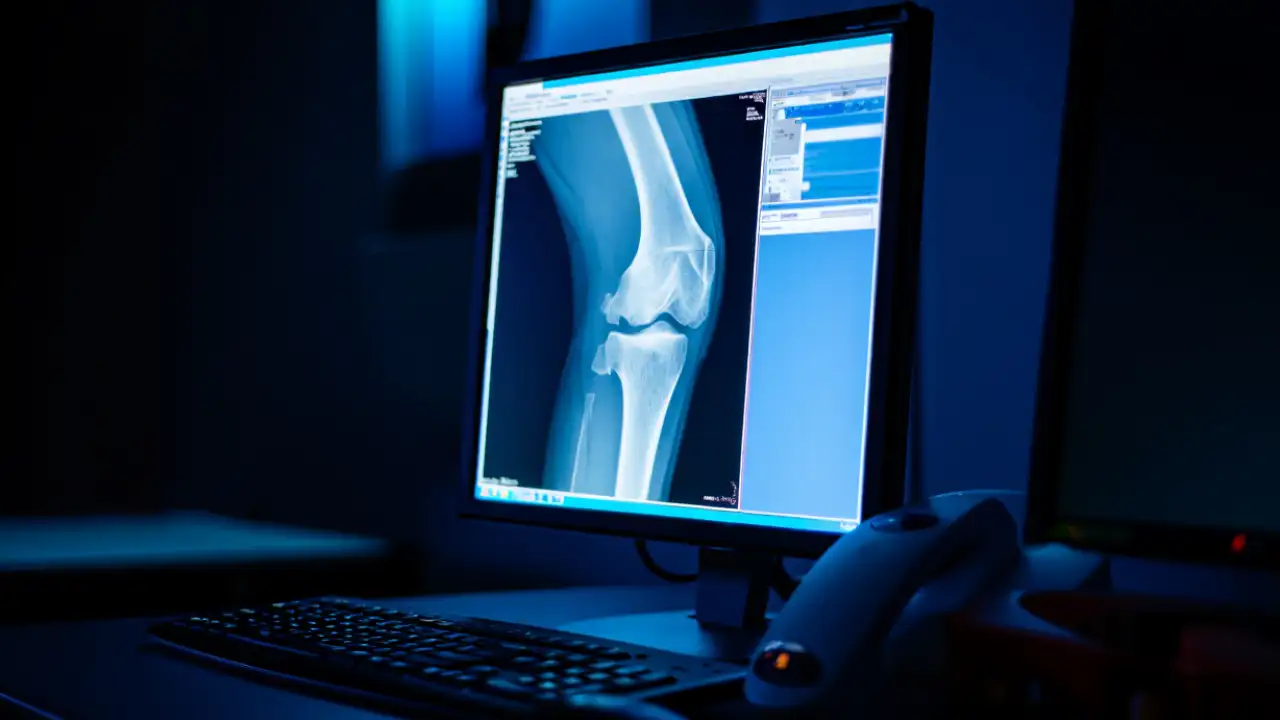

Когда врач назначает рентген пациенту с артритом, он не может полноценно увидеть состояние мягких тканей, поскольку рентгеновские лучи гораздо лучше работают с твердыми тканями, такими как кости. Мягкие ткани пропускают большую часть лучей насквозь. Без соответствующего контрастного вещества лучшее, что может сделать врач, — это оценить расстояние между костями и предположить степень тяжести артрита.

В своей лаборатории профессор Амбика Баджпайей сосредоточилась на использовании того, что большая часть мягких тканей организма заряжена отрицательно. В хряще, который служит амортизатором между суставами, отрицательный заряд помогает ткани восстанавливать свою форму после нагрузки. Фактически, более 50% жесткости ткани обусловлено именно этим эффектом. Отрицательные частицы отталкивают другие отрицательные частицы, но притягиваются к положительным. Именно поэтому исследователи химически сконструировали новый положительно заряженный контраст.

В настоящее время визуализация сустава требует введения йодсодержащего химиката, чтобы рентгеновские лучи могли «увидеть» сустав. Но хрящ не имеет хорошего кровоснабжения, поэтому большая часть контраста вытекает в окружающие ткани. Врачам приходится вводить относительно большое количество вещества, чтобы повысить шансы на то, что часть жидкости останется в суставе.

К тому же, йод может быть вреден для людей с заболеваниями почек. Новый положительно заряженный контраст притягивается к отрицательно заряженным частицам в хряще и удерживается в суставе гораздо эффективнее. Это позволяет использовать в 40 раз меньше вещества.

После введения сустав поглощает положительно заряженный контраст примерно за два часа, после чего можно проводить рентгенографию. Предположительно, контраст распадется в организме примерно через 24 часа. Первые испытания нового агента проводились на мышах, но вскоре будут он будет проверен и на людях.